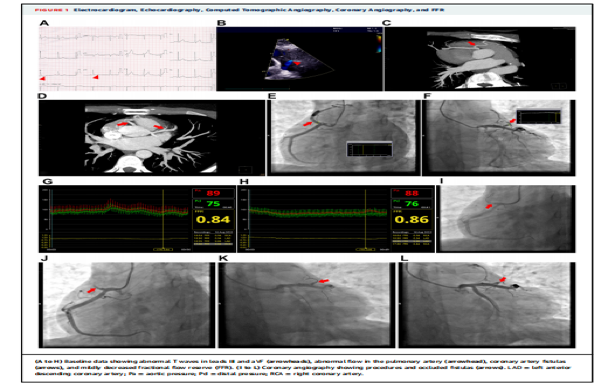

近日,由贵州省人民医院副院长吴强主任医师、心内科张陈匀主任医师团队原创的2篇“经冠脉射频消融术治疗肥厚型心肌病和冠状动脉瘘”论文在心血管病顶级期刊JACC-Cardiovascular interventions(中科院SCI期刊1区,影响因子11.075)上同期发表。这本期刊是著名的美国心脏病学会期刊(JACC)推出的专业期刊之一,也是全球阅读人数最多的的心血管期刊之一,这标志着贵州省人民医院心内科原创的经冠脉射频消融术达到世界先进水平。

经冠脉射频消融术是由省医心内科原创的一项技术,最早于2002年进行动物试验,并在临床实践中成功用于冠脉动脉穿孔、肥厚型心肌病和冠状动脉瘘的介入治疗,均取得了极佳的临床疗效。

冠脉动脉穿孔、肥厚型心肌病和冠状动脉瘘的介入治疗是心血管领域的难点,已有的介入治疗方法有栓塞物(弹簧圈、明胶海绵、自体脂肪、血栓等)封堵、酒精化学消融及外科手术等,但都存在着疗效欠佳、费用昂贵、手术时间长等不足。经过二十多年的探索和总结,经冠脉射频消融术被证实是一种安全、有效、经济、便捷的冠脉动脉穿孔、肥厚型心肌病和冠状动脉瘘的介入治疗手段。